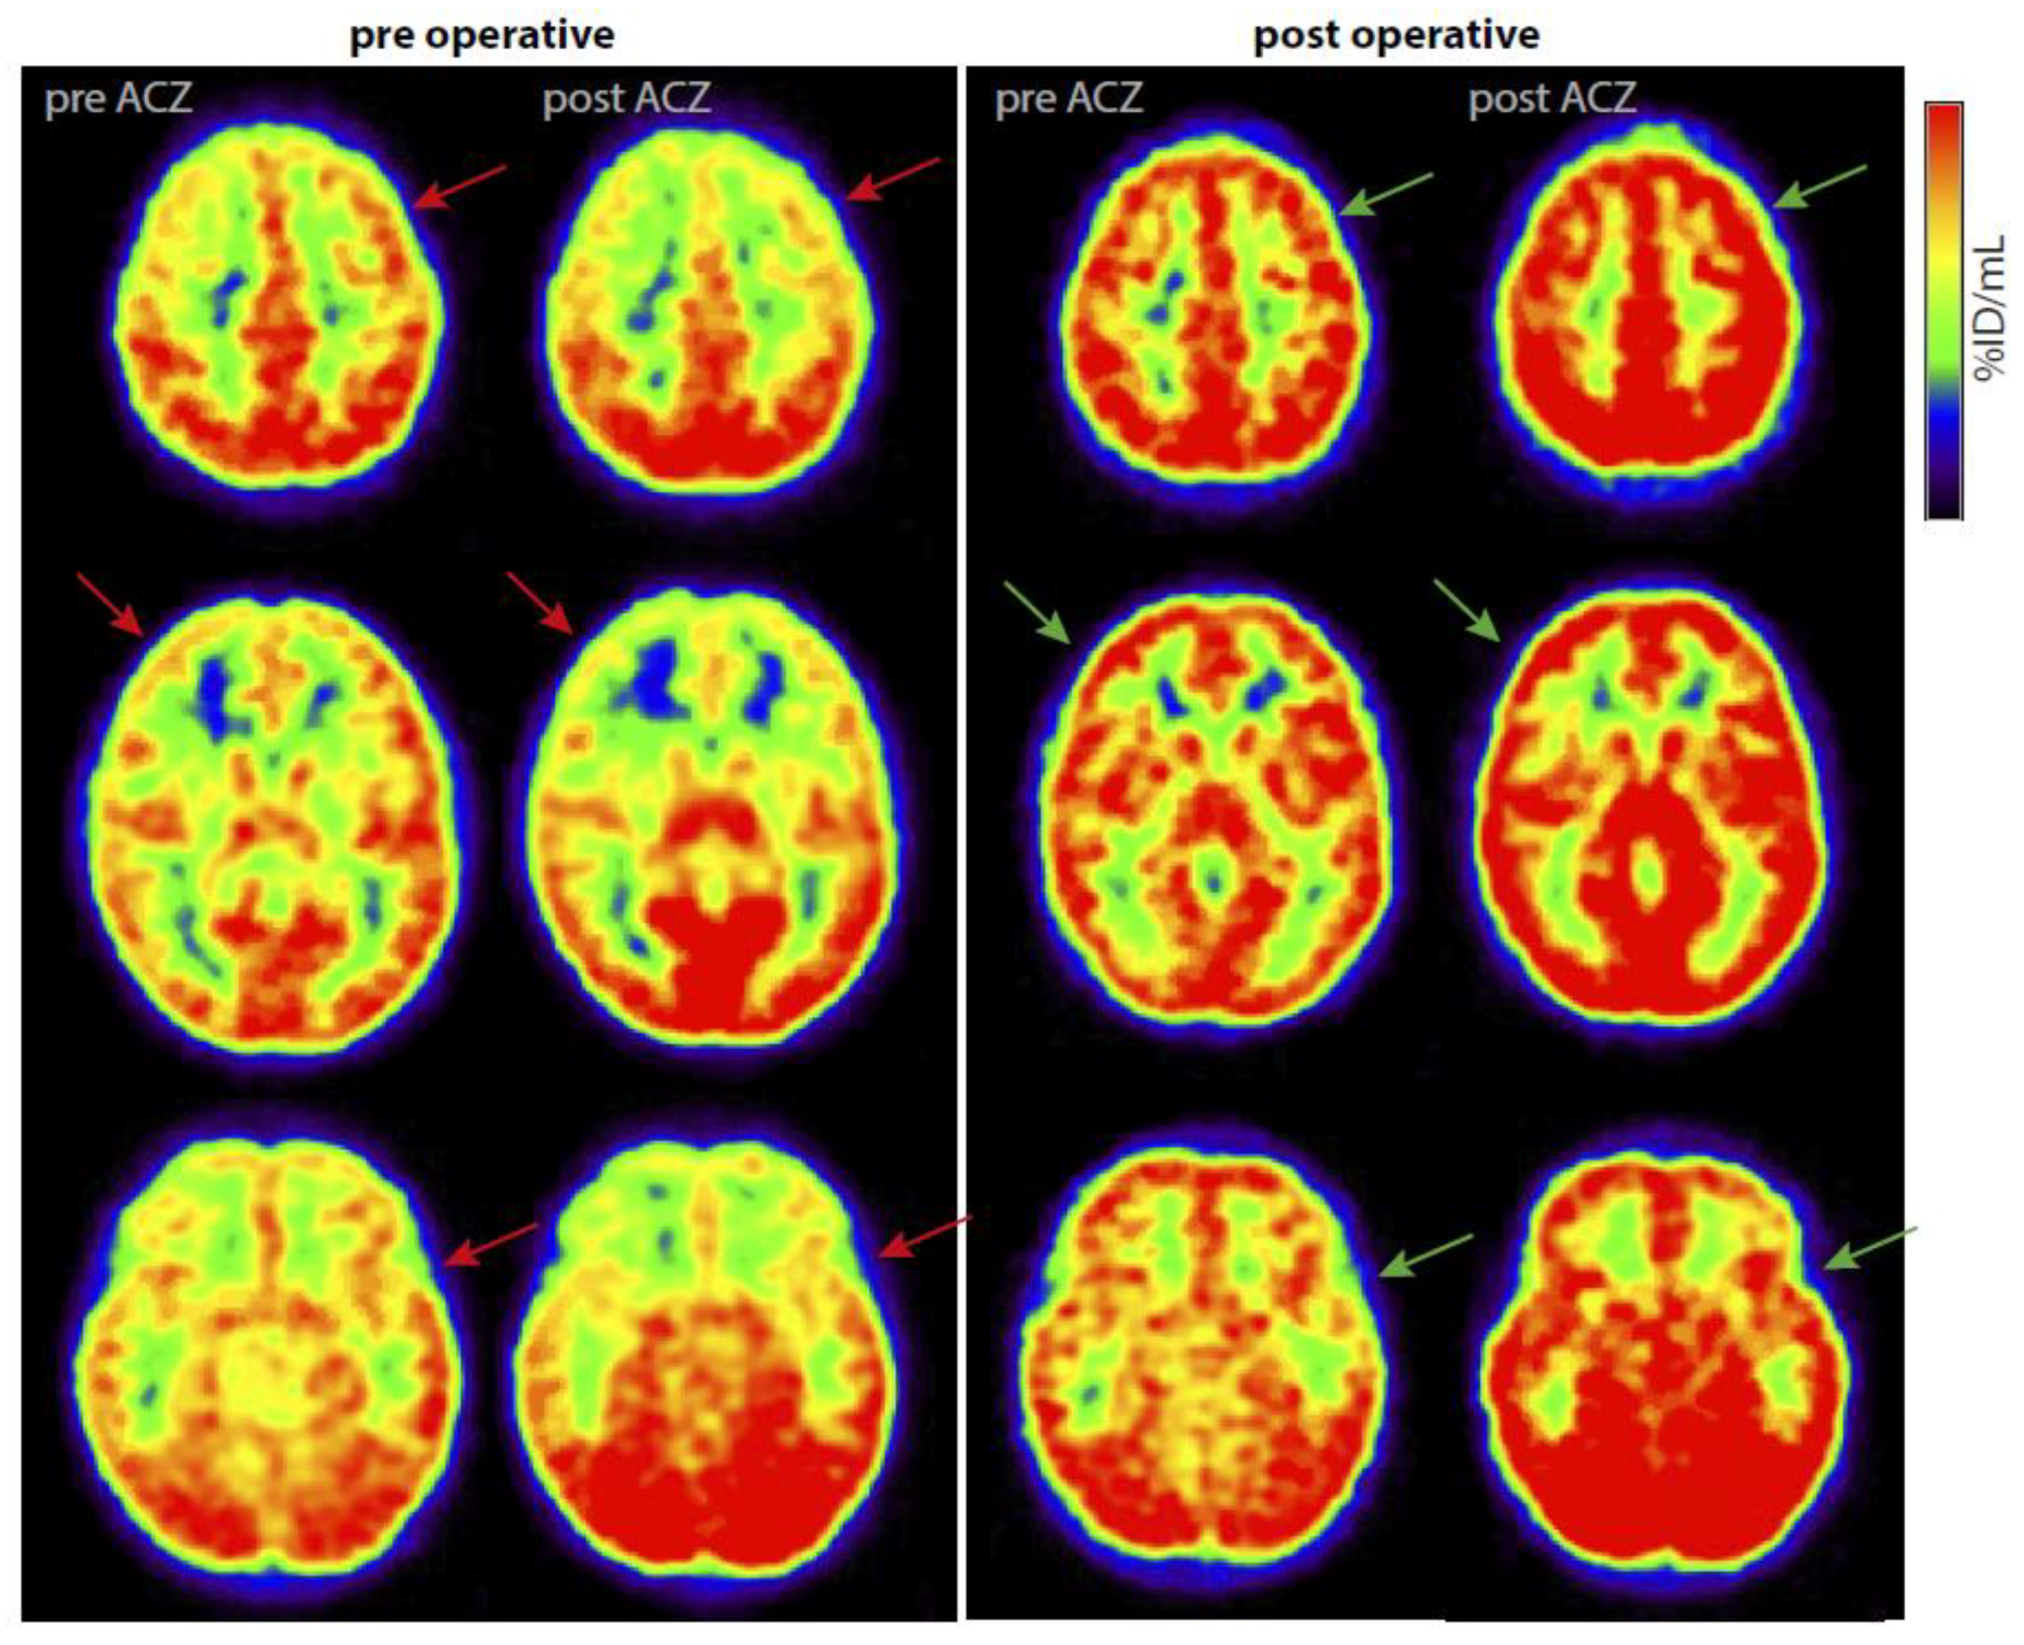

3.7. Imaging